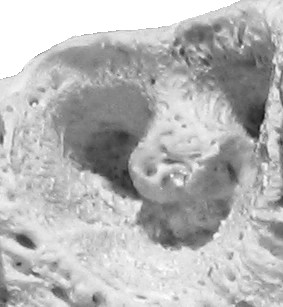

![]() Alveola of the second premolar tooth in a bovine maxillary bone | |

Dental alveoli (singular alveolus) are sockets in the jaws in which the roots of teeth are held in the alveolar process with the periodontal ligament. The lay term for dental alveoli is tooth sockets. A joint that connects the roots of the teeth and the alveolus is called a gomphosis (plural gomphoses). Alveolar bone is the bone that surrounds the roots of the teeth forming bone sockets.

In mammals, tooth sockets are found in the maxilla, the premaxilla, and the mandible.